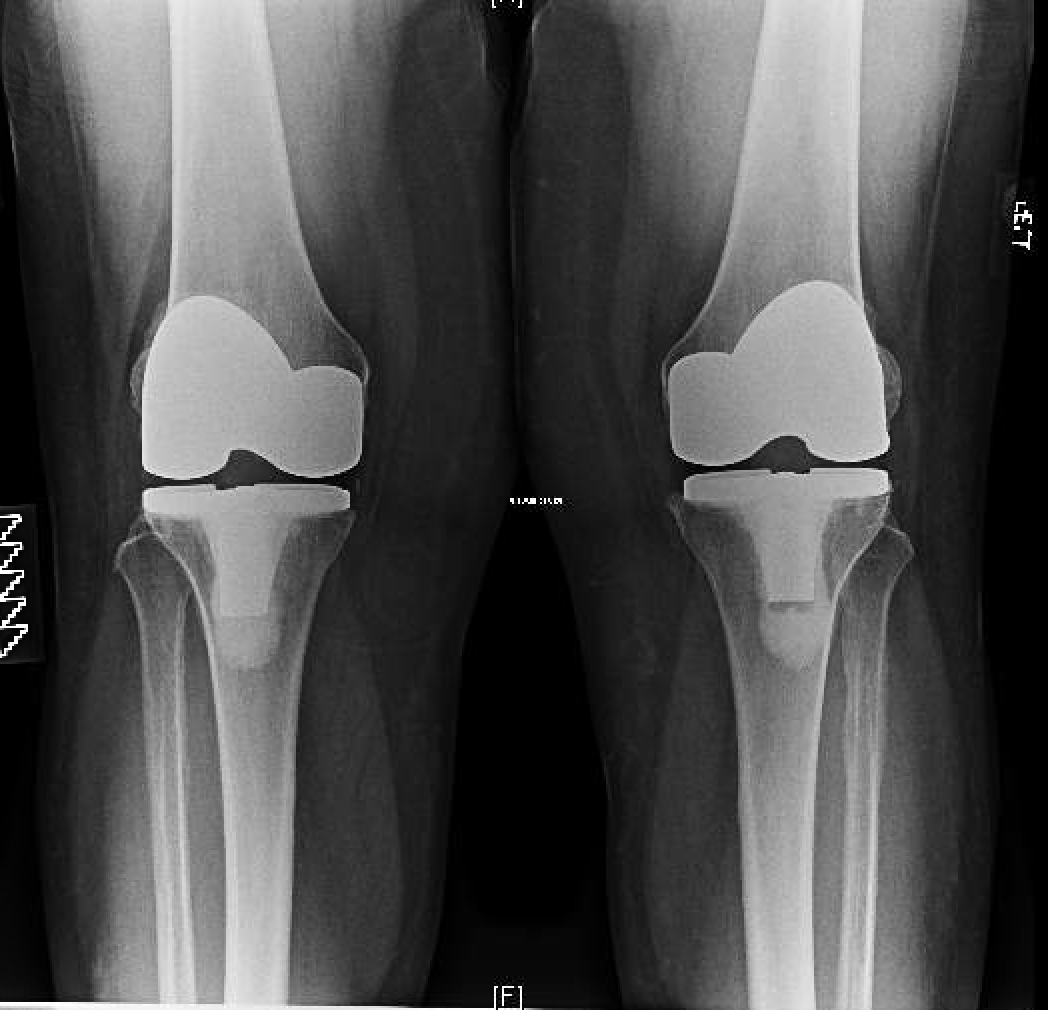

BILATERAL KNEE REPLACEMENT

"Enjoying Every Minute of It"

After many years of discomfort with both knees, endless amounts of injections, and getting nowhere I met Mr Vioreanu at the Sports Surgery Clinic in December 2014.

BILATERAL TKR SURGERY

"Back to playing bowls pain free"

At 82 years of age I had both my knees replaced at Santry Sports Clinic by Mr. Mihai Vioreanu, who came highly recommended. I had my first consultation with Mr.Vioreanu in mid-july 2016, and was very impressed with how he explained the whole procedure to me, including the emphasis he put on the importance of doing the exercises, both pre and post op. Very down to earth, and made me feel, ‘ok let’s go, let’s get on with it’.

BILATERAL SIMULTANEOUS KNEE REPLACEMENTS

"Pain free and no limp at 3 months"

I am 40 years old and Mihai performed bilateral, simultaneous full knee replacement surgery for me just over three months ago. The surgery was a complete success. I now walk pain free and without any limp. I am living my life to the full again. I will be forever grateful for the outstanding level of care I received from Mihai and his clinical and admin teams.

"Enjoying a whole New Way of Life"

On the 27 January 2016 I had a decision to make - my two knees had been paining me for the last 5 years - but in the past year they had gotten considerably worse, to the point where I found it difficult to walk or play golf. I checked the Sport Surgery Clinic in Santry and reading Mr. Mihai Vioreanu's web page, I was very impressed by his experience of hip and knee replacement surgery.

"There is nothing I can't do"

At one year after surgery, I can say it was the best thing I did as I never looked back. I am active and still working full time. There is nothing I can't do.